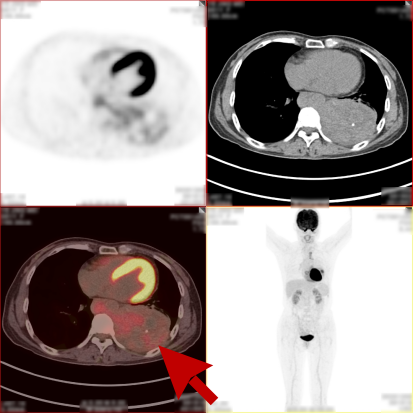

病史:女,51岁,左侧胸腔肿物约3-4年,干咳伴左侧胸痛1个月余,自服药物不能缓解。2023.12.6 CT 显示左侧胸腔及纵隔内肿块,考虑肿瘤性病变,胸膜来源低度恶性肿瘤(胸膜间皮瘤)可能。无其他病史,进食可,二便可,今年以来有体重减轻,为鉴别病灶良恶性申请PET/CT检查。

PET/CT检查所见

PET/CT诊断意见:

1、左侧胸腔内混杂密度肿块,实性组织代谢轻中度增高,考虑间叶组织来源低度恶性肿瘤,病灶内部分组织坏死,与左侧胸膜粘连并向纵隔内生长;

2、纵隔(1L、2L、3A、6、8R 组)及左侧锁骨上窝多发淋巴结转移灶;

3、胸 8 椎体左份结节状高代谢病灶,考虑骨转移灶。

PET/CT活检病理:恶性畸胎瘤